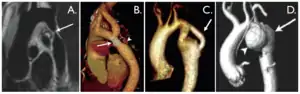

| کوارکتاسیون آئورت. A. 'لکه خون سیاه' نمای ساژیتال مایل یک کوارتاکسیون شدید و مجزا را در نوار مرزی آئورت نشان میدهد(فلش). B.سیتی آنژیوگرام سهبعدی(با تصحیح کنتراست) استنت را نشان میدهد(فلش) که بخشی از سابکلاوین چپ را دربر گرفته. نوک پیکان یک شبه آنوریسم را در انتهای دیستال استنت نشان داده است. C. امآر آنژیوگرام در خم آئورت یک هیپوپلازی و کوارکتاسیون را نشان داده(فلش). D. آنژیوگرام سهبعدی شبهآنئوریسم(نوک پیکان) پس از آنژیوپلاستی در مرحله پیشین. لومن اصلی قابل دیدن است(فلش). | |